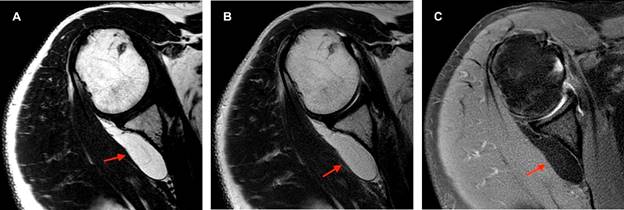

En el estudio de resonancia magnética entre fibras musculares del infraespinoso se observa imagen ovoidea, de márgenes bien delimitados, isointensa al tejido graso en secuencias T1, T2 y densidad protónica con saturación grasa, con diámetros aproximados en plano axial de 5.5 × 1.3 cm, en plano sagital de 3.1 × 1.4 cm y en coronal de 3.8 × 2.9 cm, con imágenes lineales internas hipointensas en todas las secuencias menores de 2 mm (Figura 1). La lesión se extiende por toda la fosa infraespinosa con involucro de algunas fibras musculares del redondo menor y desplaza levemente el infraespinoso (Figura 2).

Figura 1: Imágenes en plano axial. A) T1, B) T2 y C) densidad de protones con saturación grasa (DP FAT SAT). Muestran la lesión (flecha roja) ovoidea, de comportamiento graso, con delgadas líneas hipointensas en su periferia correspondientes a fibras musculares del infraespinoso.